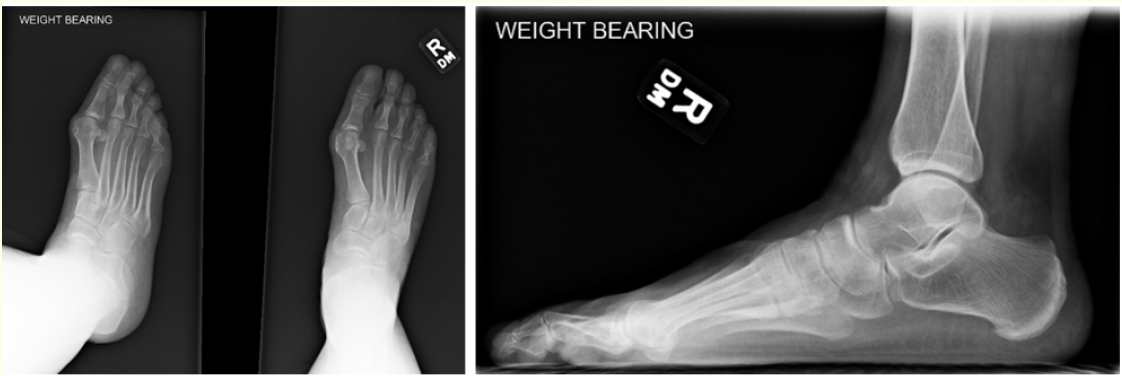

Middle Cuneiform Stress Fracture in a Postal Worker: A Case Report

Stephanie N Campbell, Jacob M Jones, Raul Aviles, Loren K Spencer and John J Anderson. 13(11): 37-40.